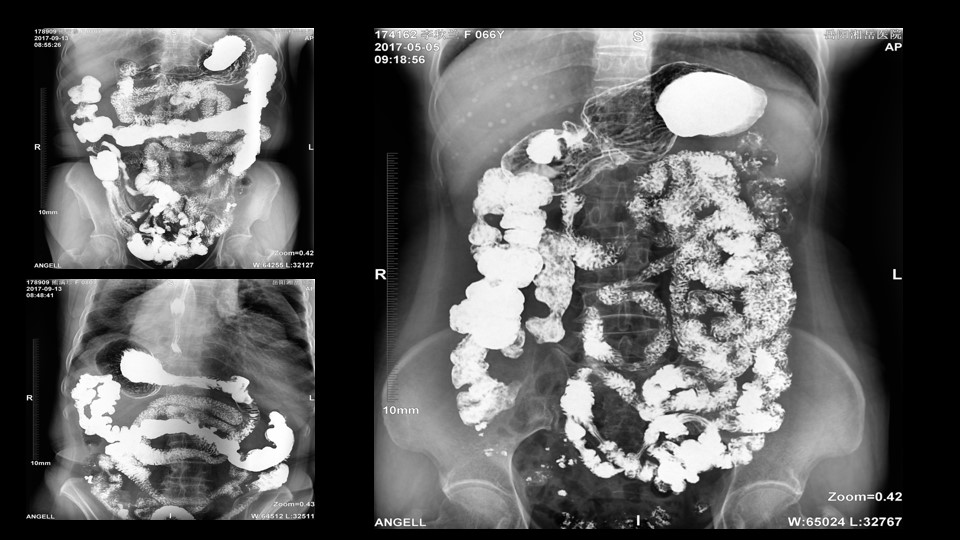

会议开始,岳阳市医学会放射分会副主委、湘岳医院放射科蔡雨主任,结合自身在放射影像的20多年经验,为参会嘉宾分享了动态DR在消化道造影中的应用价值。作为动态DR用户,蔡雨主任结合动态DR的实际拍片与操控经验,分享了动态DR技术在相关群体疾病检查上的独到优势和人文关怀。蔡雨主任说到:“随着内镜技术的发展以及CT、MR的发展,消化道造影在减少,但是这并不意味着消化道造影的价值在下降。以老年人为例,很多老年群体都患有严重的心肺疾病、或者消化道畸形,很多老年人本身就有糖尿病、高血压等等综合疾病,传统内镜的检查对于这类群体来说是一件难以忍受的痛苦,而动态DR的多项创新技术让这类群体的消化系统疾病筛查变得更为人性和精准。任何一个好的消化道造影,一定是患者、诊断医生、临床医生三方满意的结果。388vip太阳集团科技动态DR技术利用900万像素高清拍片、大幅面透视、高清点片、视频保存与回放等核心功能,完全满足临床对消化道气钡双重造影检查的需要。图像质量全面超越以往模拟胃肠机、影增数字胃肠机”。蔡雨主任全面演示了动态DR在食道造影、上消化道造影、小肠双对比造影、结肠气钡双对比造影中的应用,通过动态DR可以清晰获得临床诊断和评估的图像依据。

蔡雨主任使用动态造影图像示例